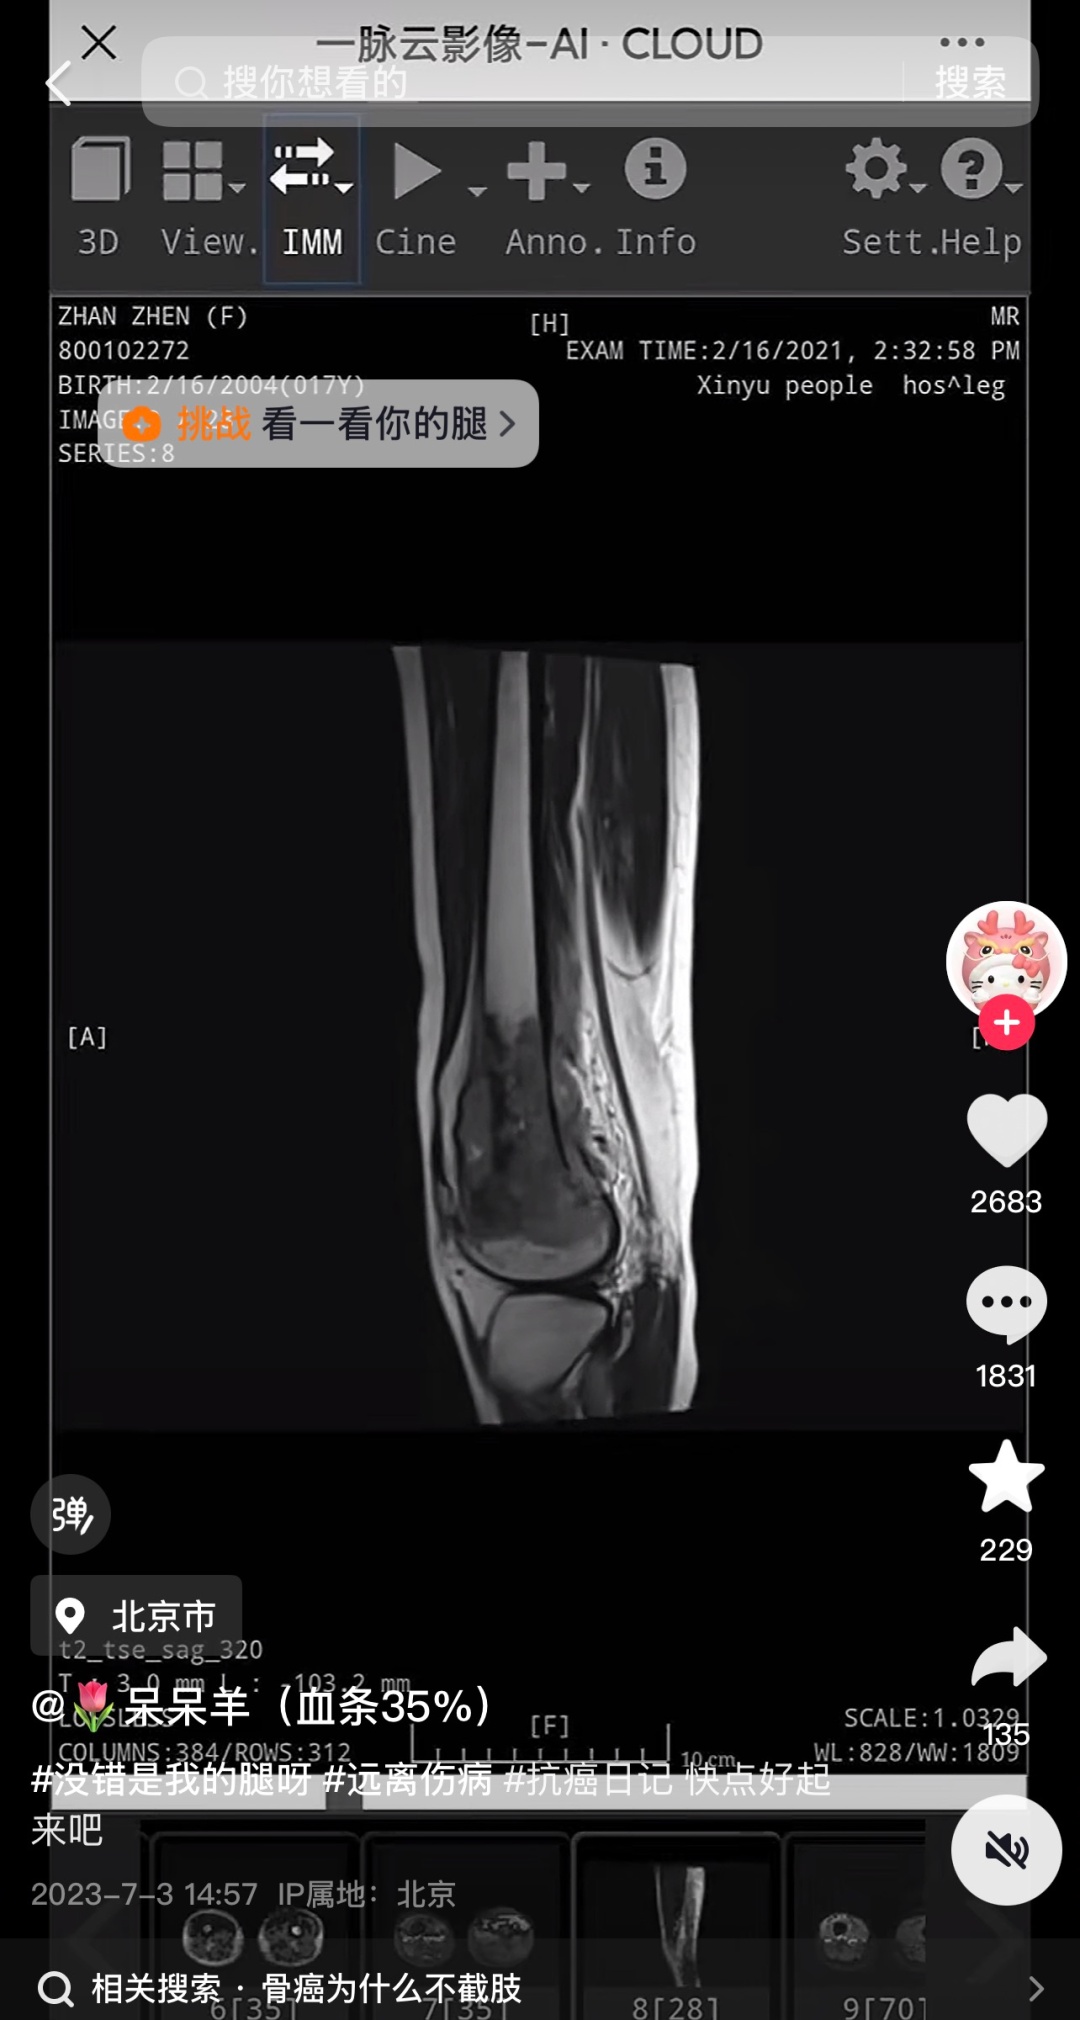

记者发现,网红“呆呆羊(血条35%)”抖音账号有16.7万粉丝,2023年7月3日,“呆呆羊”更新首条内容,视频中“呆呆羊”发布了自己的诊断报告,时间为2021年2月16日。